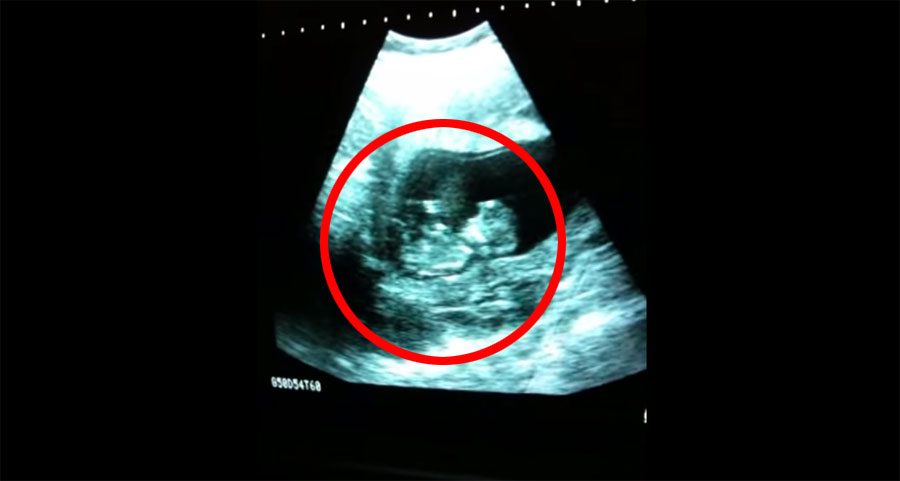

Una pareja visitó a su ginecólogo para obtener una rutinaría ecografía de su pequeña con la esperanza de verla. No se imaginaban lo que sucedería después, algo tremendamente sorprendente…

Así es: ¡la ecografía captó como su hija estaba jugando en el vientre de su madre!

Aunque es algo sorprendente de ver, en realidad es bastante común. Los bebés dentro del vientre de su madre hacen un montón de cosas inusuales y divertidas. De hecho, se ponen a chupar sus pulgares, estornudan, tienen sueño, e incluso pueden ser sorprendidos por ruidos que oyen del exterior o por movimientos bruscos de mamá.

Y, por supuesto, también juegan, que es lo que se ve en este vídeo. Según la mayoría de médicos, que un bebé juegue y de patadas en el útero es una buena señal, significa que el bebé es feliz y está sano.